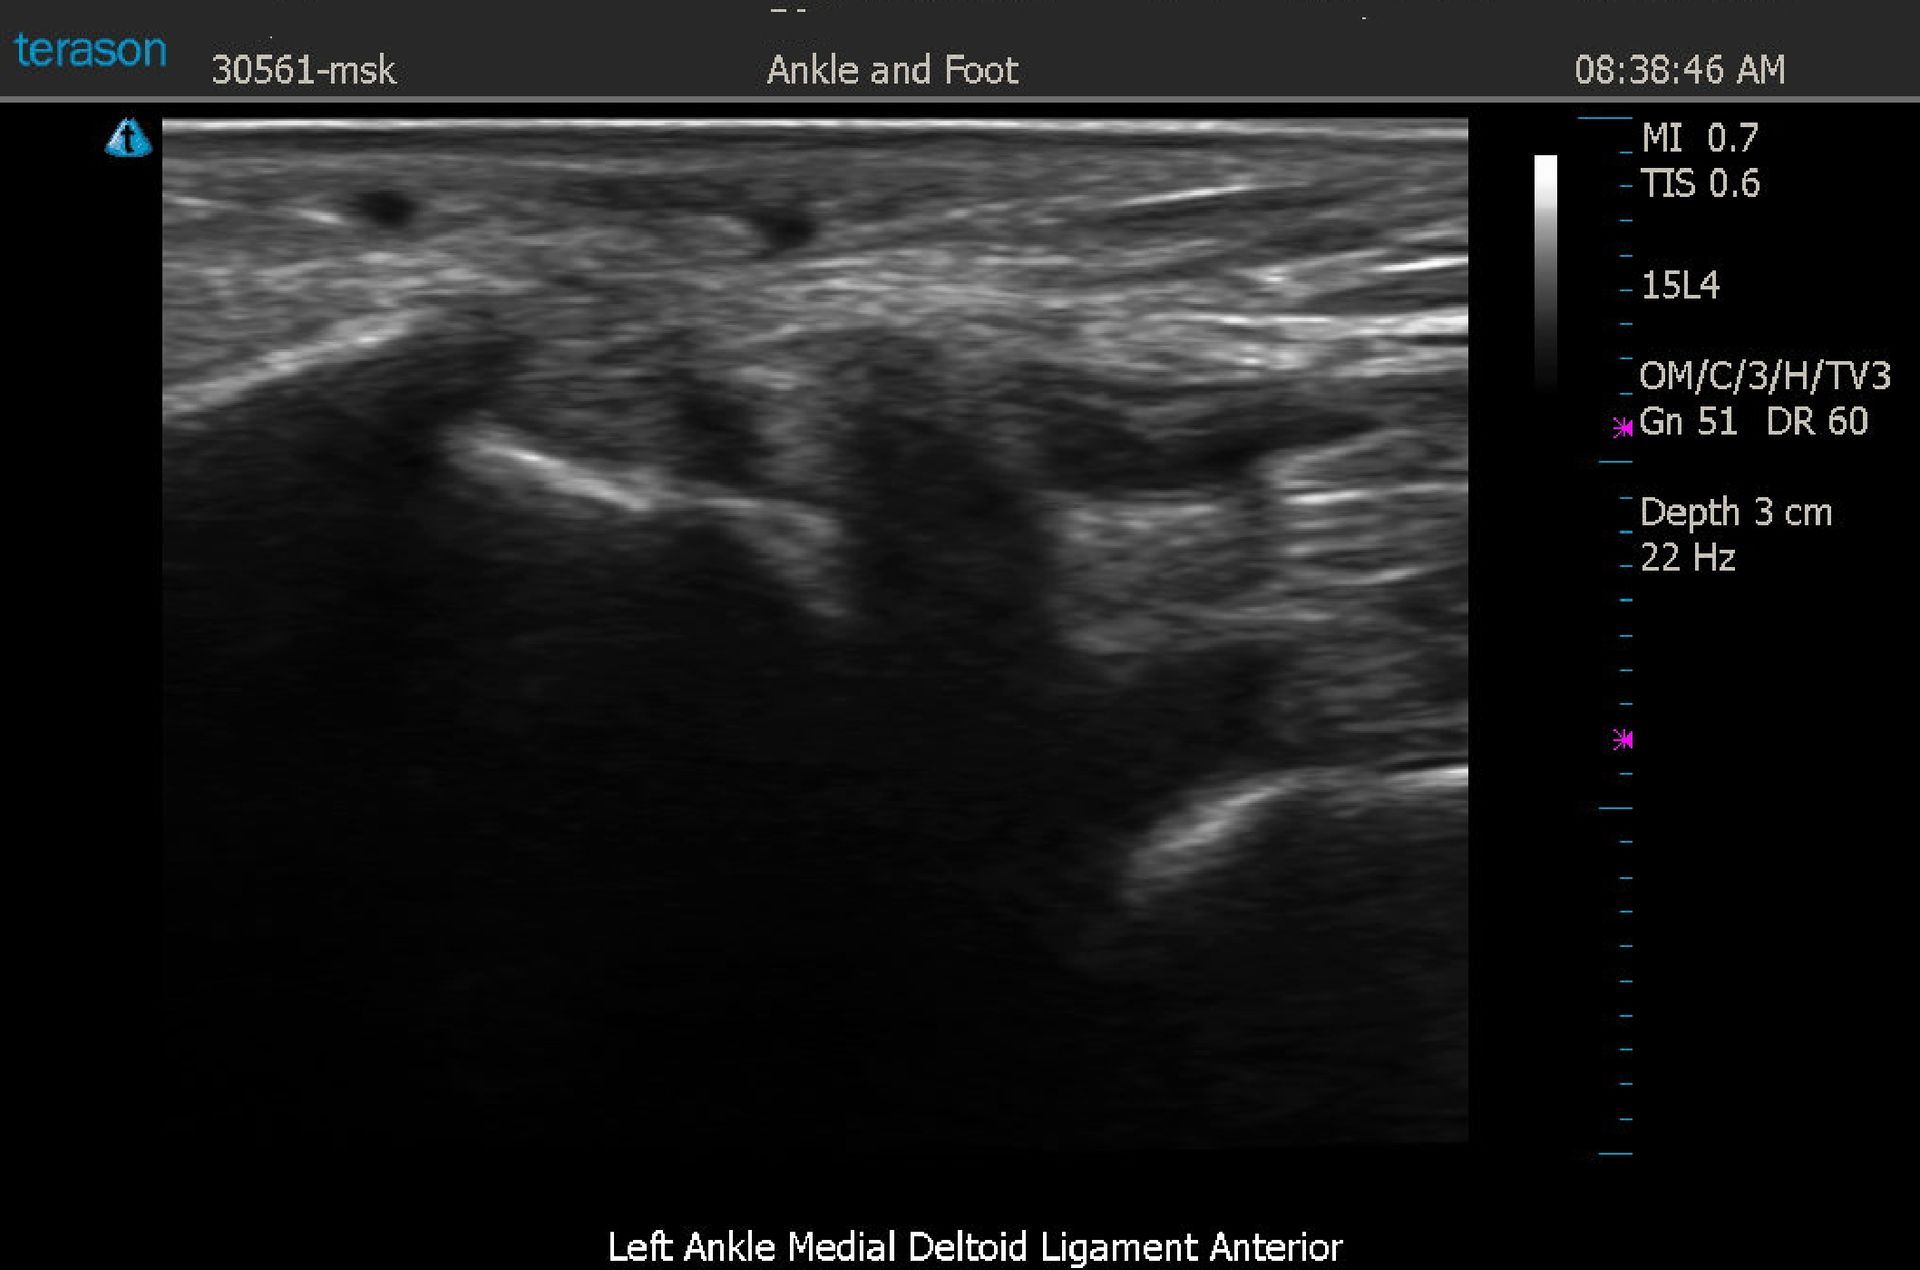

56 yo female with a chief complaint of BLE pain. Symptoms originally began after right knee arthroscopy and spread to involve the RLE proximal to the knee, the low back, and the entire LLE. She also admits to a left foot fracture three years ago. Cold stress sympathetic skin response thermology showed an asymmetry pattern over the heel and medial aspect of the ankle. Thermographic impression restated findings. Clinical Impression was: a localized sympathetic pain syndrome of the left ankle should be considered; there may be both CCC and ABC components. DX MSK US confirmed a Medial Deltoid ligament strain.